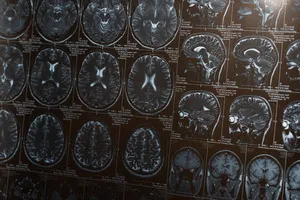

MRI(자기 공명영상) 검사는 강력한 자기장과 라디오파를 이용해 우리 몸속을 생생하게 들여다보는 최첨단 영상 검사입니다. 뇌, 척수, 관절 등 다양한 부위의 질환을 조기에 발견하고 정확하게 진단하는 데 필수적입니다.

MRI 검사는 CT 검사보다 훨씬 더 세밀한 영상을 제공하여, 마치 우리 몸의 지도를 보듯이 각 조직과 기관의 미세한 차이까지 파악할 수 있습니다. 뇌종양, 뇌출혈, 척추 디스크, 관절염 등 다양한 질환의 정확한 위치와 크기를 정밀하게 확인하여, 환자에게 꼭 맞는 최적의 치료 계획을 세우는 데 결정적인 역할을 합니다.